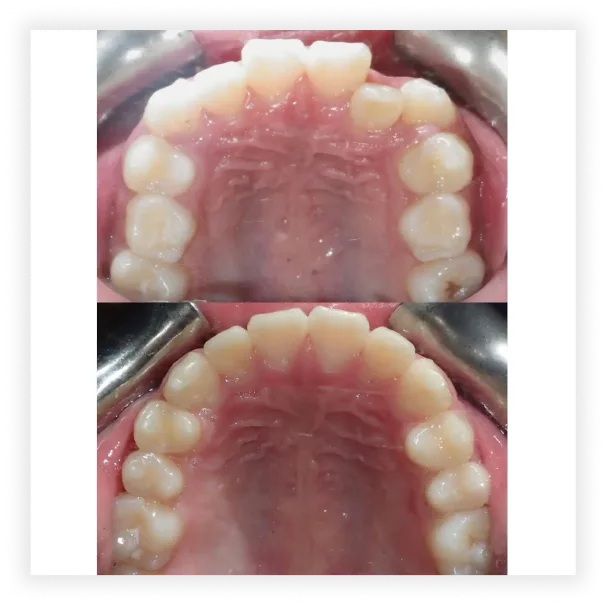

Take a look at some of our cases and successful transformations below.

Case #2

Final Photos